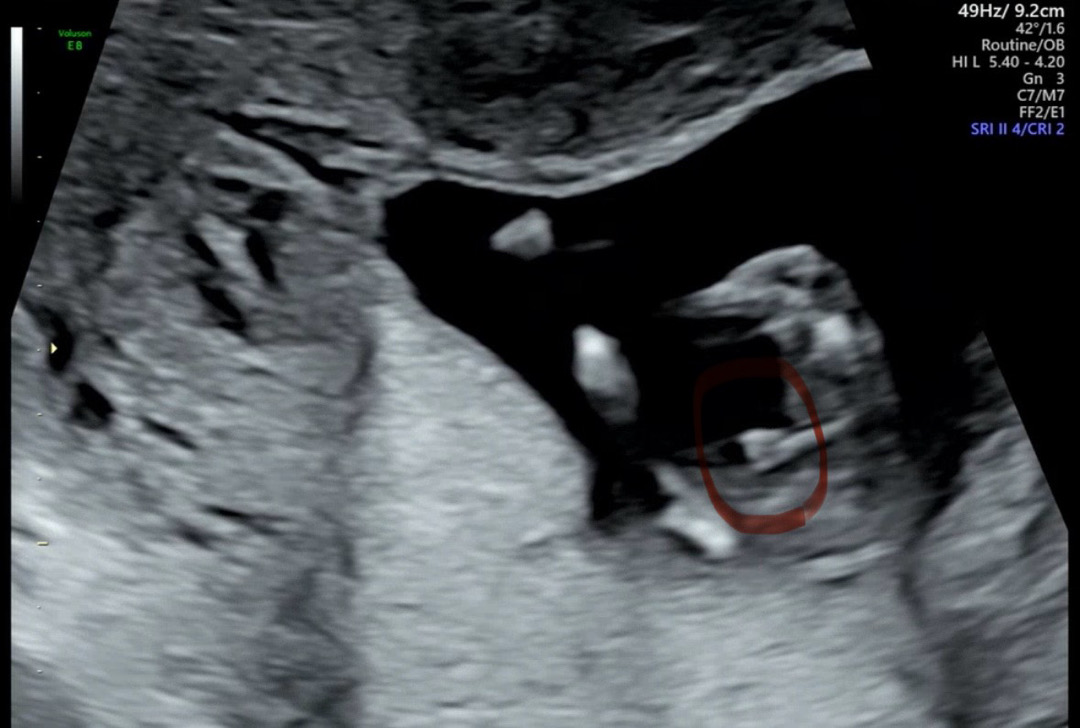

13주 성별 어때보이시나요!!

아직 이르지만 병원에선 다리사이에 뭐가 보인다고 하긴 했는데.. 어찌보이시나요 ㅎㅎㅎ